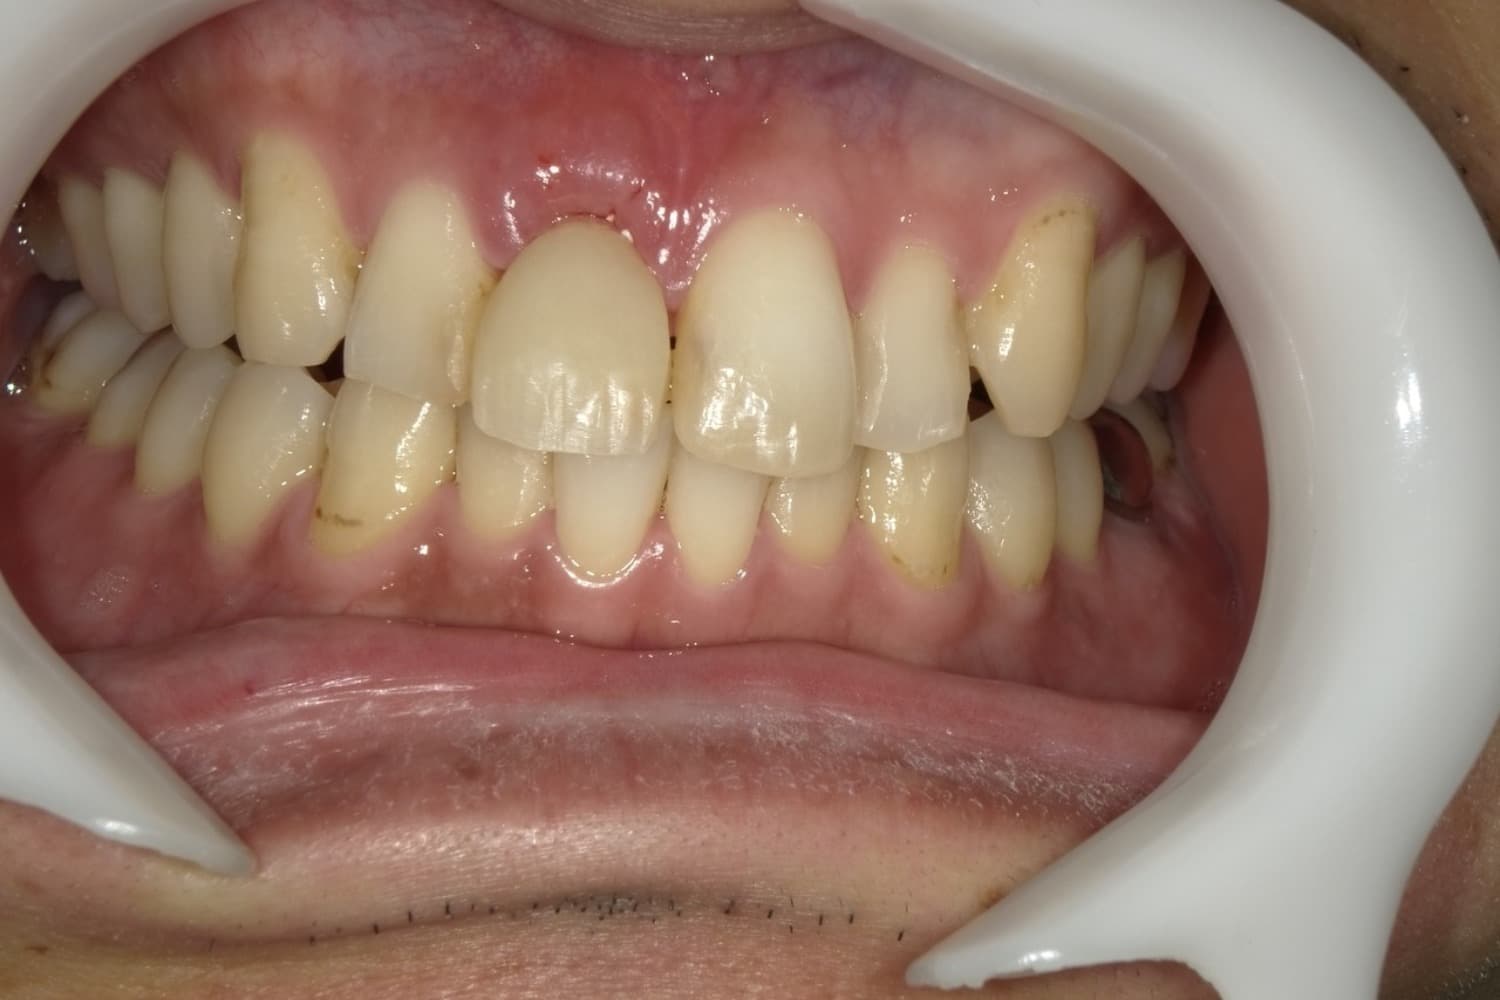

歯根破折した前歯のインプラント治療(30代男性)

Before

外傷によって歯根破折した前歯を抜歯してインプラント治療をおこなう(当日に仮歯の装着までおこなう)。

年齢

30代

性別

男性

主訴

外傷によって歯根破折している。

治療期間

2ヵ月半

治療回数

6回

費用

385000円(税込) 費用の内訳: 【インプラント基本料】330000円(税込み) 基本料金に以下を含む ・フィックスチャー及び手術費用 ・投薬費用、 ・レントゲン費用 ・インプラント上部費用(アバットメントおよびジルコニアクラウンの費用用) 【オプション費用】 ・抜歯即時埋入・即時負荷加算(プロビショナルレストレーション費用・人工骨費用・暫間アバットメント費用・抜歯費用を含む)55000円(税込)

副作用・リスク

・手術後に痛み・腫れ・出血・合併症等を引き起こす恐れがあります。 ・噛む感覚がご自身の歯と異なることがあります。 ・見た目がご自身の歯と異なる場合があります。 ・手術後もメインテナンスを続けないと、インプラントが抜け落ちてしまう恐れがあります。